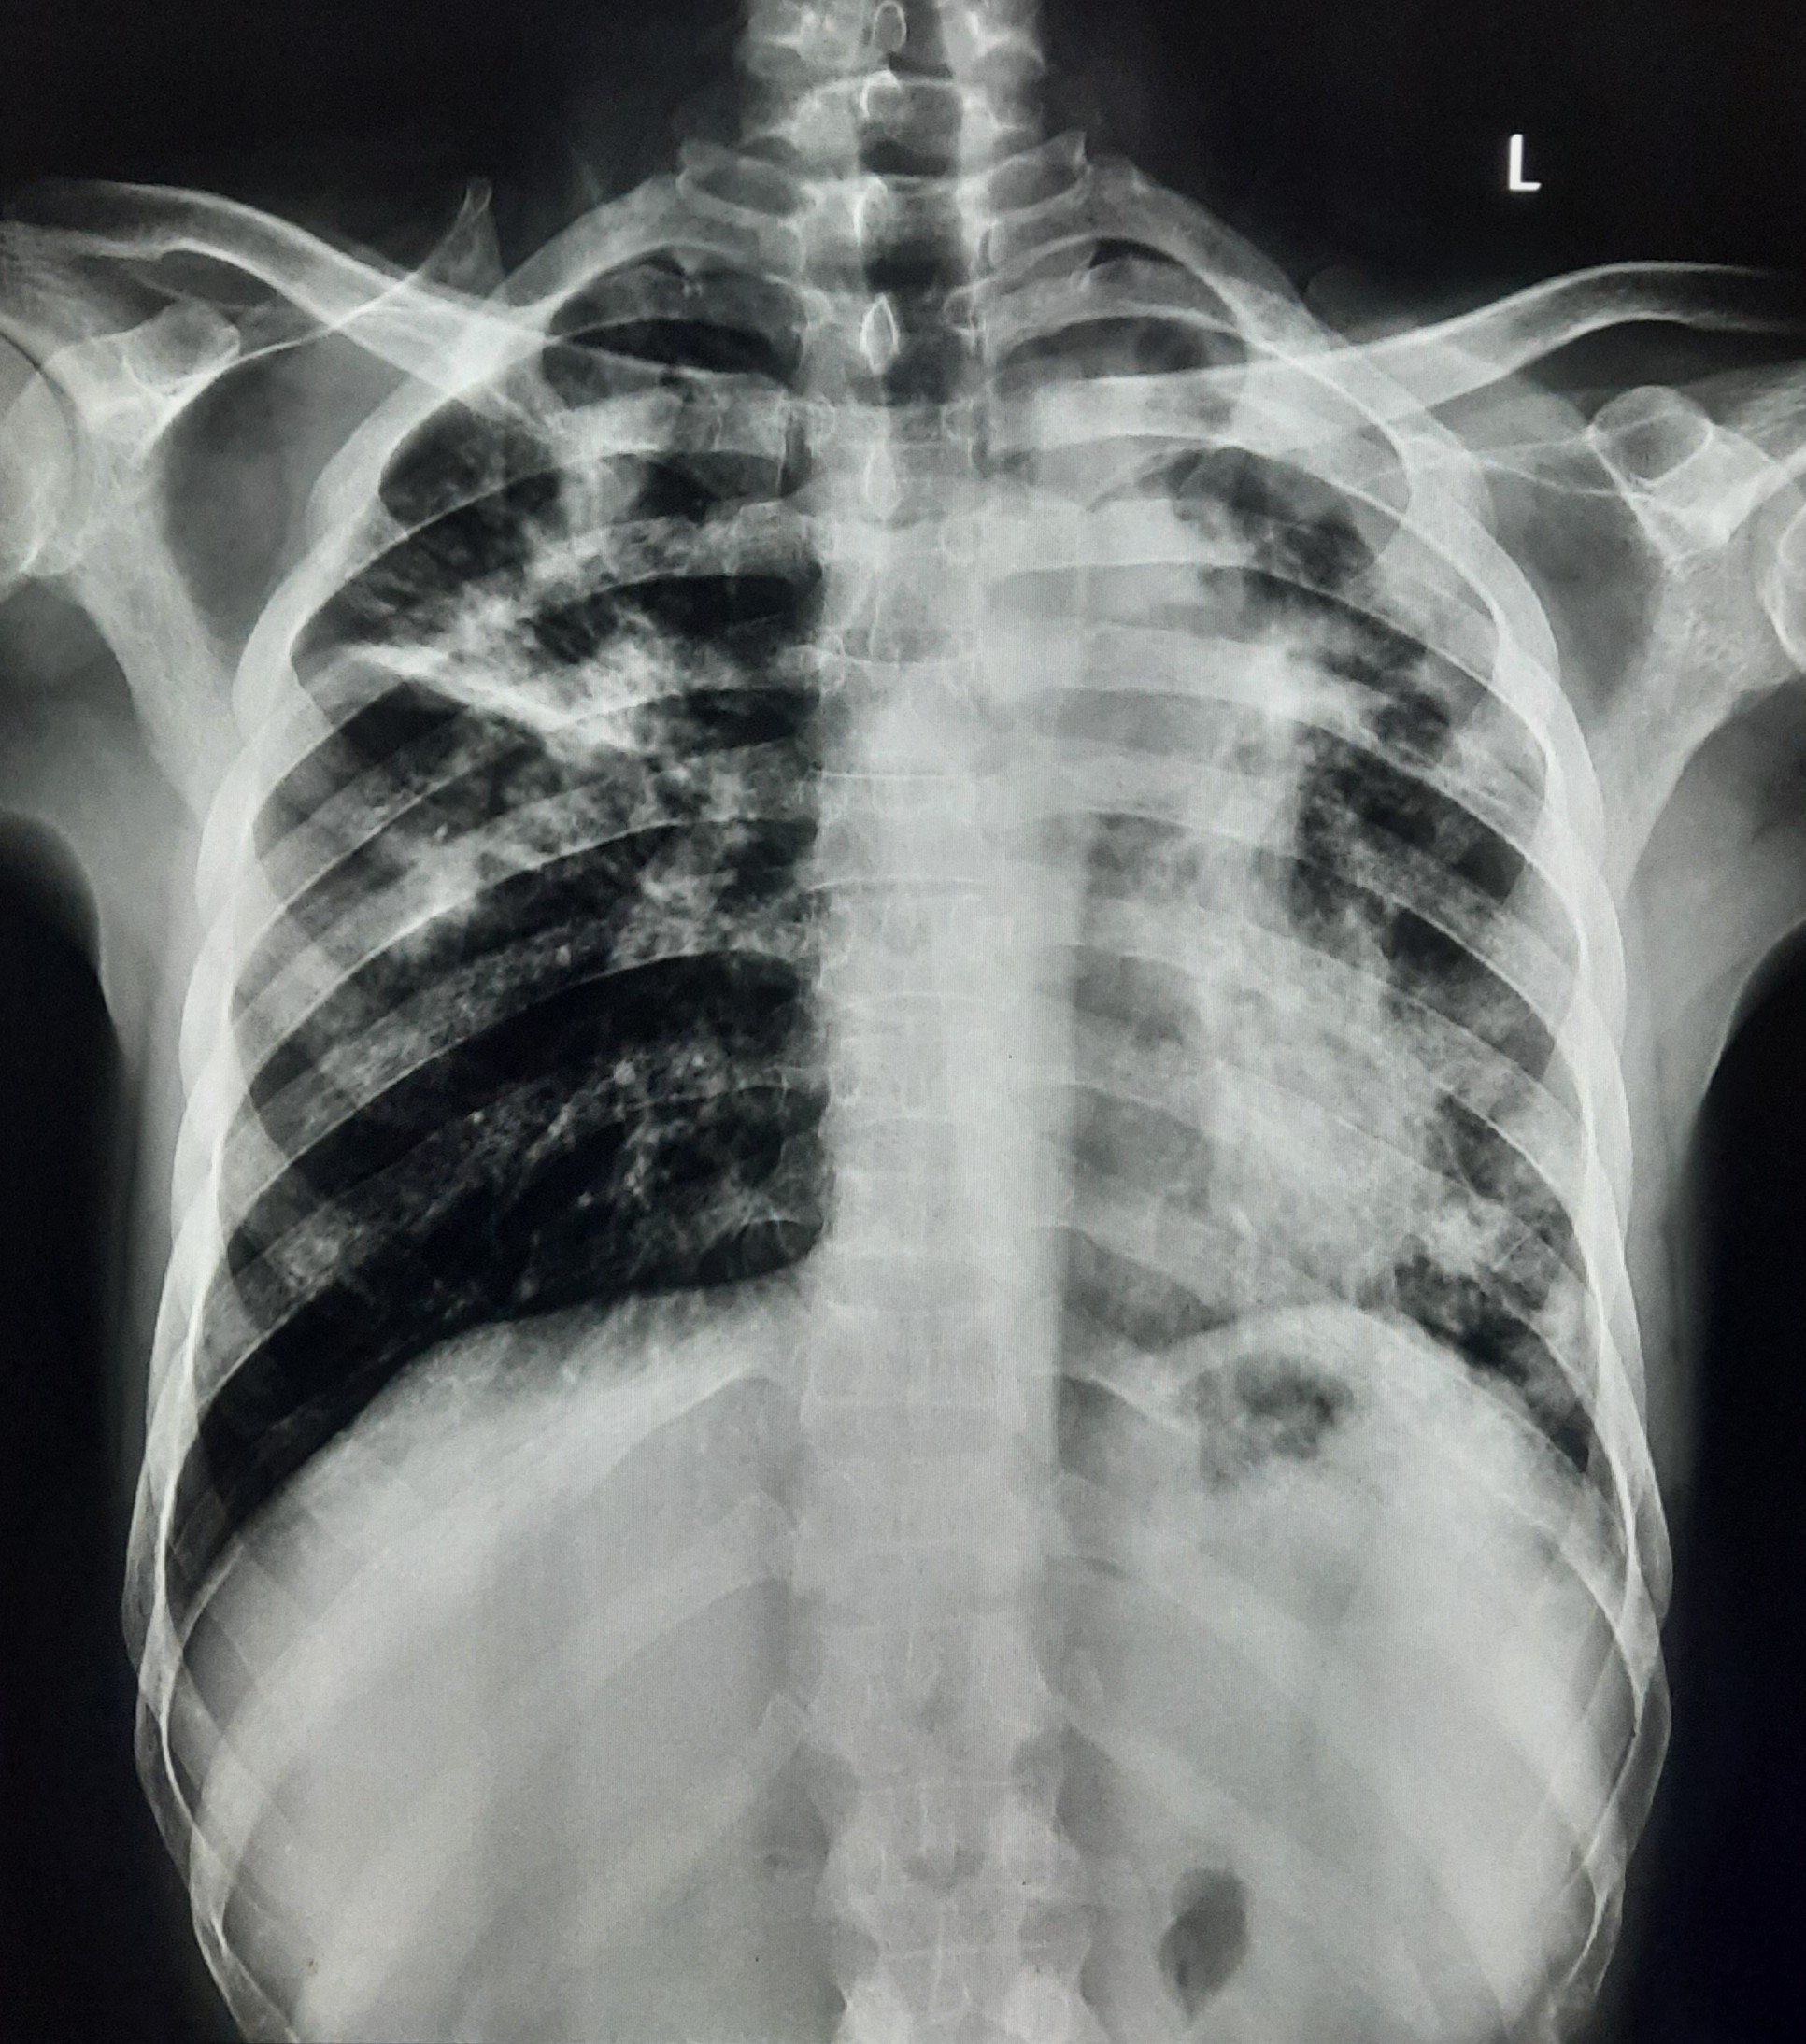

| 107 | IGGMC, Nagpur, Nagpur | P2 | 29-4365 | Vivek Indurkar | Consent taken on Paper | 36 Yrs. |

Provisional Diag : PTB Reactivation

Final Diag : Post TB With Reactivation |

TB Case (Confirmed) | Right lung fibro-bronchial and Fibro-calcific changes, fibro-cavitary changes In Right, Infiltration In Left Upper zone | Abnormality visible on x-ray |